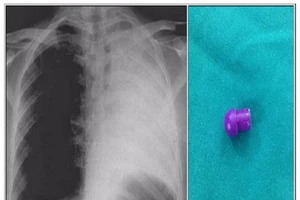

Xẹp phổi trái vì nuốt phải đầu bút bi